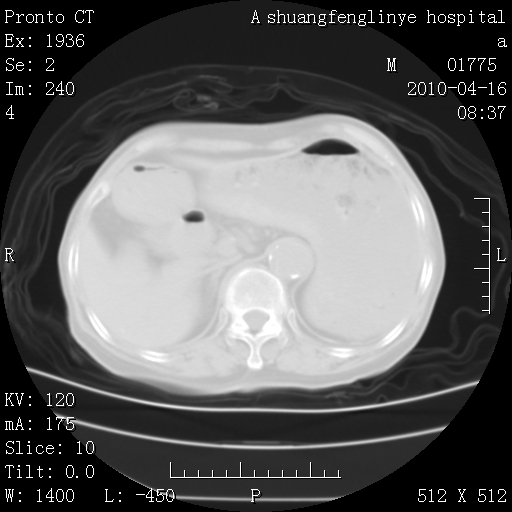

陈旧性结核,胃腔扩大,脾脏受压后移

典型 夹层动脉瘤。 内膜瓣钙化移位